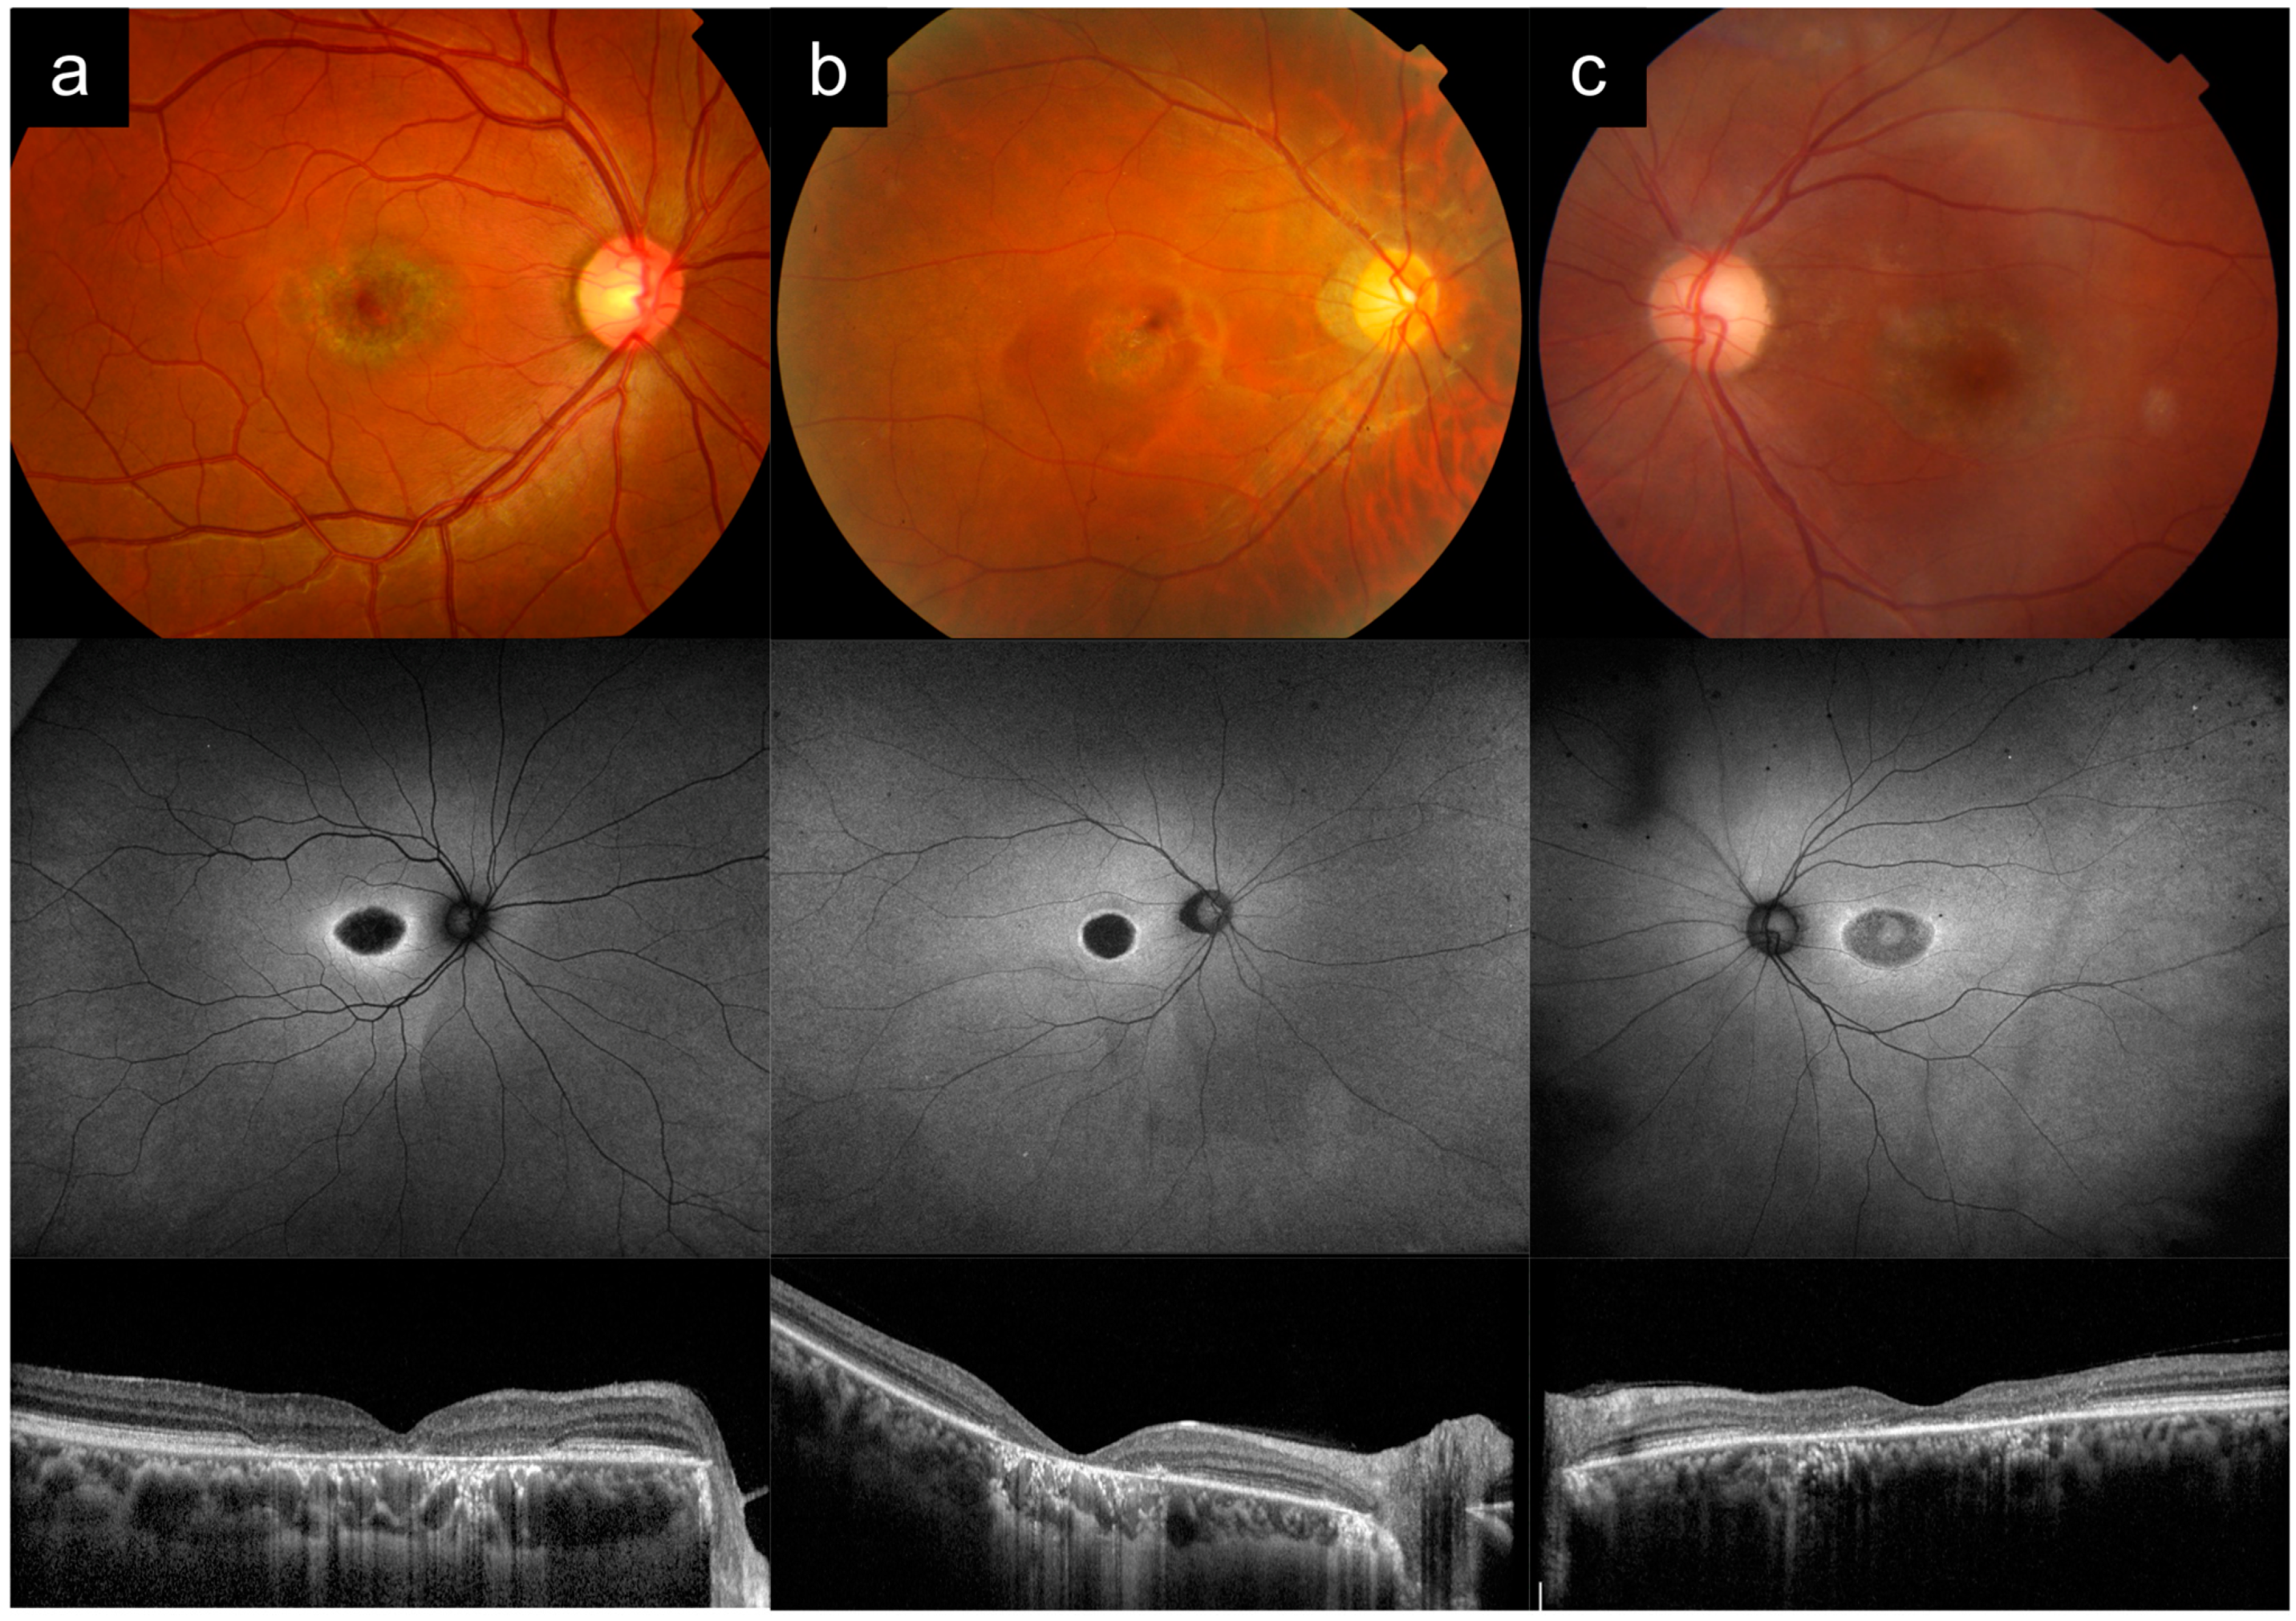

Case 2a presented with difficulty reading at 20 years old. There were no other affected family members, which was consistent with AR inheritance.

Figure 2a shows multimodal imaging from the right eye in his 20s. VA in the right eye varied from 6/12 to 6/15 at the time. CFP imaging demonstrates a central area of RPE atrophy at the fovea, with a slight metallic sheen, but without flecks. AF imaging shows a central oval hypo-AF region corresponding to the foveal atrophy, surrounded by a hyper-AF ring, and similarly confirms the absence of flecks. OCT imaging shows a central area of RPE and outer retinal atrophy. ERG showed mainly macular dysfunction, with mild/borderline reduction in full-field cone responses and normal rod function. Genetic testing revealed an

ABCA4 genotype (

Table 1).

Case 2b presented with poor vision noted in school around 10 years old, with progressive hemeralopia and glare. BCVA in his 20s was 6/60 and 6/45 in the right and left eyes, respectively. Pedigree analysis revealed 6 other affected family members in two generations, with male-to-male transmission, indicating AD inheritance.

Figure 2b shows imaging from his 20s. CFP imaging shows a central area of RPE atrophy. AF imaging shows a central round hypo-AF region corresponding to the area of atrophy surrounded by a brighter hyper-AF ring. OCT imaging shows a central area of RPE and outer retinal atrophy. ERG showed significant reduction in full-field cone responses and macular function, with normal/borderline rod responses. Genetic testing identified the pathogenic

GUCY2D c.2512c>T p.R838C allele.

Case 2c presented with blurred vision at 62 years old. She had no family history of ocular disease, but she a history of rheumatoid arthritis, being treated with hydroxychloroquine for more than 10 years. She was diagnosed with hydroxychloroquine toxicity and the medication was stopped.

Figure 2c shows images from the left eye when she was 72 years old. VA in that eye was 6/15 at the time. CFP imaging shows an area of foveal RPE atrophy in a bull’s eye pattern. AF imaging shows a bull’s eye pattern with central hyper-AF, surrounded by a zone of hypo-AF, and an outside hyper-AF ring. OCT imaging shows perifoveal outer retinal atrophy, with some relative sparing of the subfoveal region.

Case 2a demonstrates

ABCA4-RD with a phenotype of Stargardt disease without flecks, or bull’s eye maculopathy, which can be easily mistaken for cone dystrophy, such as the phenotype of Case 2b, which was a

GUCY2D-associated AD cone dystrophy. Note that the appearance on imaging for both cases are very similar, especially on AF and OCT. Key distinguishing features between Cases 2a and 2b are the clinical symptoms, appearance of the atrophy, ERG findings, and inheritance patterns (

Table 2). Prominent symptoms of glare and hemeralopia, significantly diminished full-field cone responses, and the AD inheritance pattern in Case 2b point towards AD cone dystrophy, rather than

ABCA4-associated Stargardt disease. Case 2c shows that systemic drug toxicity is another important cause of bull’s eye maculopathy and can present with similar imaging features that mimic IRD. This serves as an important reminder that drug toxicity must be excluded in all such cases.